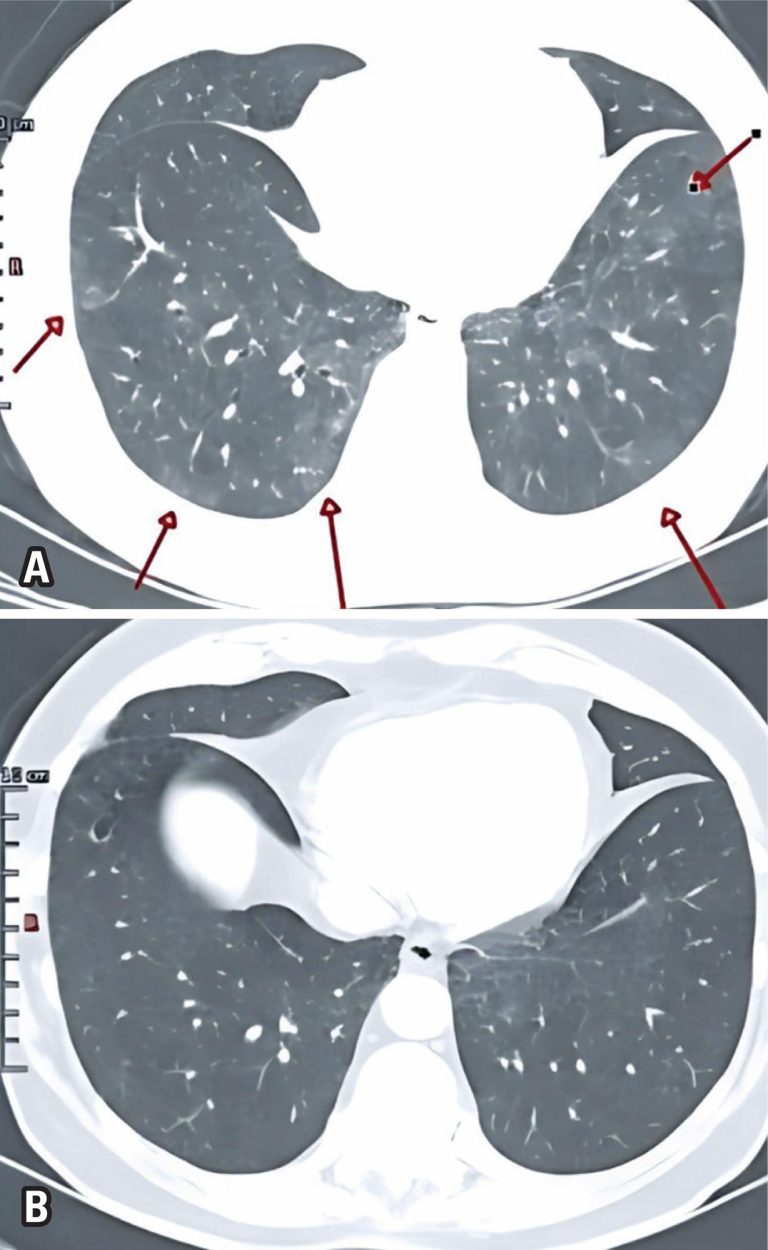

Disseminated juvenile paracoccidioidomycosis: a case report and literature review

Abstract We report a case of juvenile paracoccidioidomycosis in a previously healthy patient and aim to raise awareness of its severe and atypical clinical manifestations. A 16-year-old male student, employed in automotive cleaning services, originally from Pará and residing in Embu das Artes, São Paulo, presented with progressive lymphadenopathy, jaundice, and signs of acute liver failure. He was admitted to a tertiary hospital, where imaging and histopathological analyses confirmed the diagnosis of paracoccidioidomycosis by identifying Paracoccidioides spp. on lymph node […]